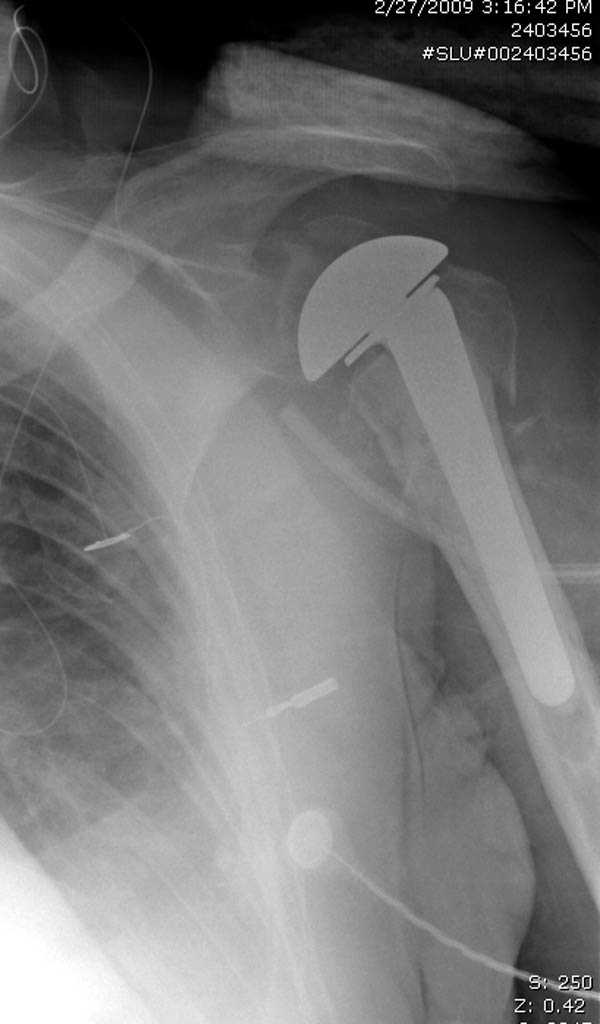

Здесь пример открытой репозиции 57 летнего с переломом плеча (1,2) смещение обнаружено на интероперационном снимке. При нормальной прямой проекция (3) угловое смещение обнаружили в аксиальной проекции (4)

дополнительные снимки по протезированию